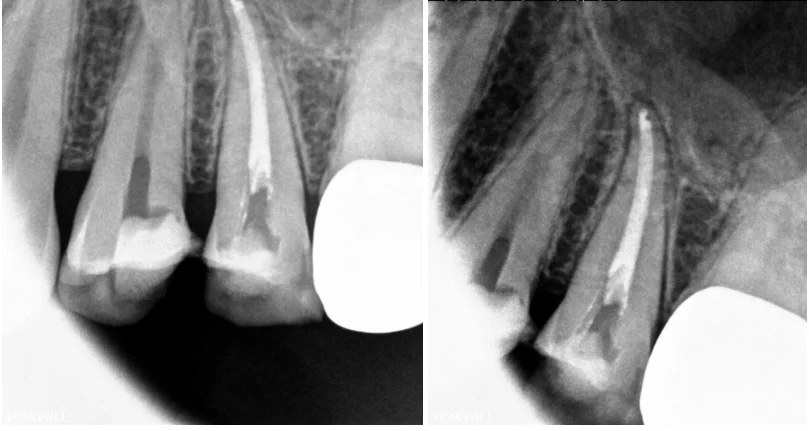

엑스레이 검사 등을 통해 확인한 결과, 현재 치료가 진행 중인 치아에서는 통증이 없었고 이미 신경치료를 마무리한 치아에서 통증을 느끼고 있는 상태였습니다.

해당 치아는 신경치료를 5~6회 정도 진행한 뒤 약 한 달 만에 마무리된 상황이었는데, 그 치아에 살짝만 닿아도 통증이 심하다고 말씀하셨습니다.

겉으로 보이는 신경치료 상태만 놓고 보면 큰 문제는 없어 보일 수 있습니다. 하지만 신경치료는 매우 미세한 세균 수준의 차이에도 결과가 달라질 수 있는 치료이기 때문에 단순한 방사선 사진만으로는 완전히 괜찮은 상태인지 확신하기 어렵습니다.

신경치료 당시 사용되었던 재료와 내부의 잔여 물질들을 모두 정리한 뒤, 재신경치료를 진행하기로 결정하였습니다.